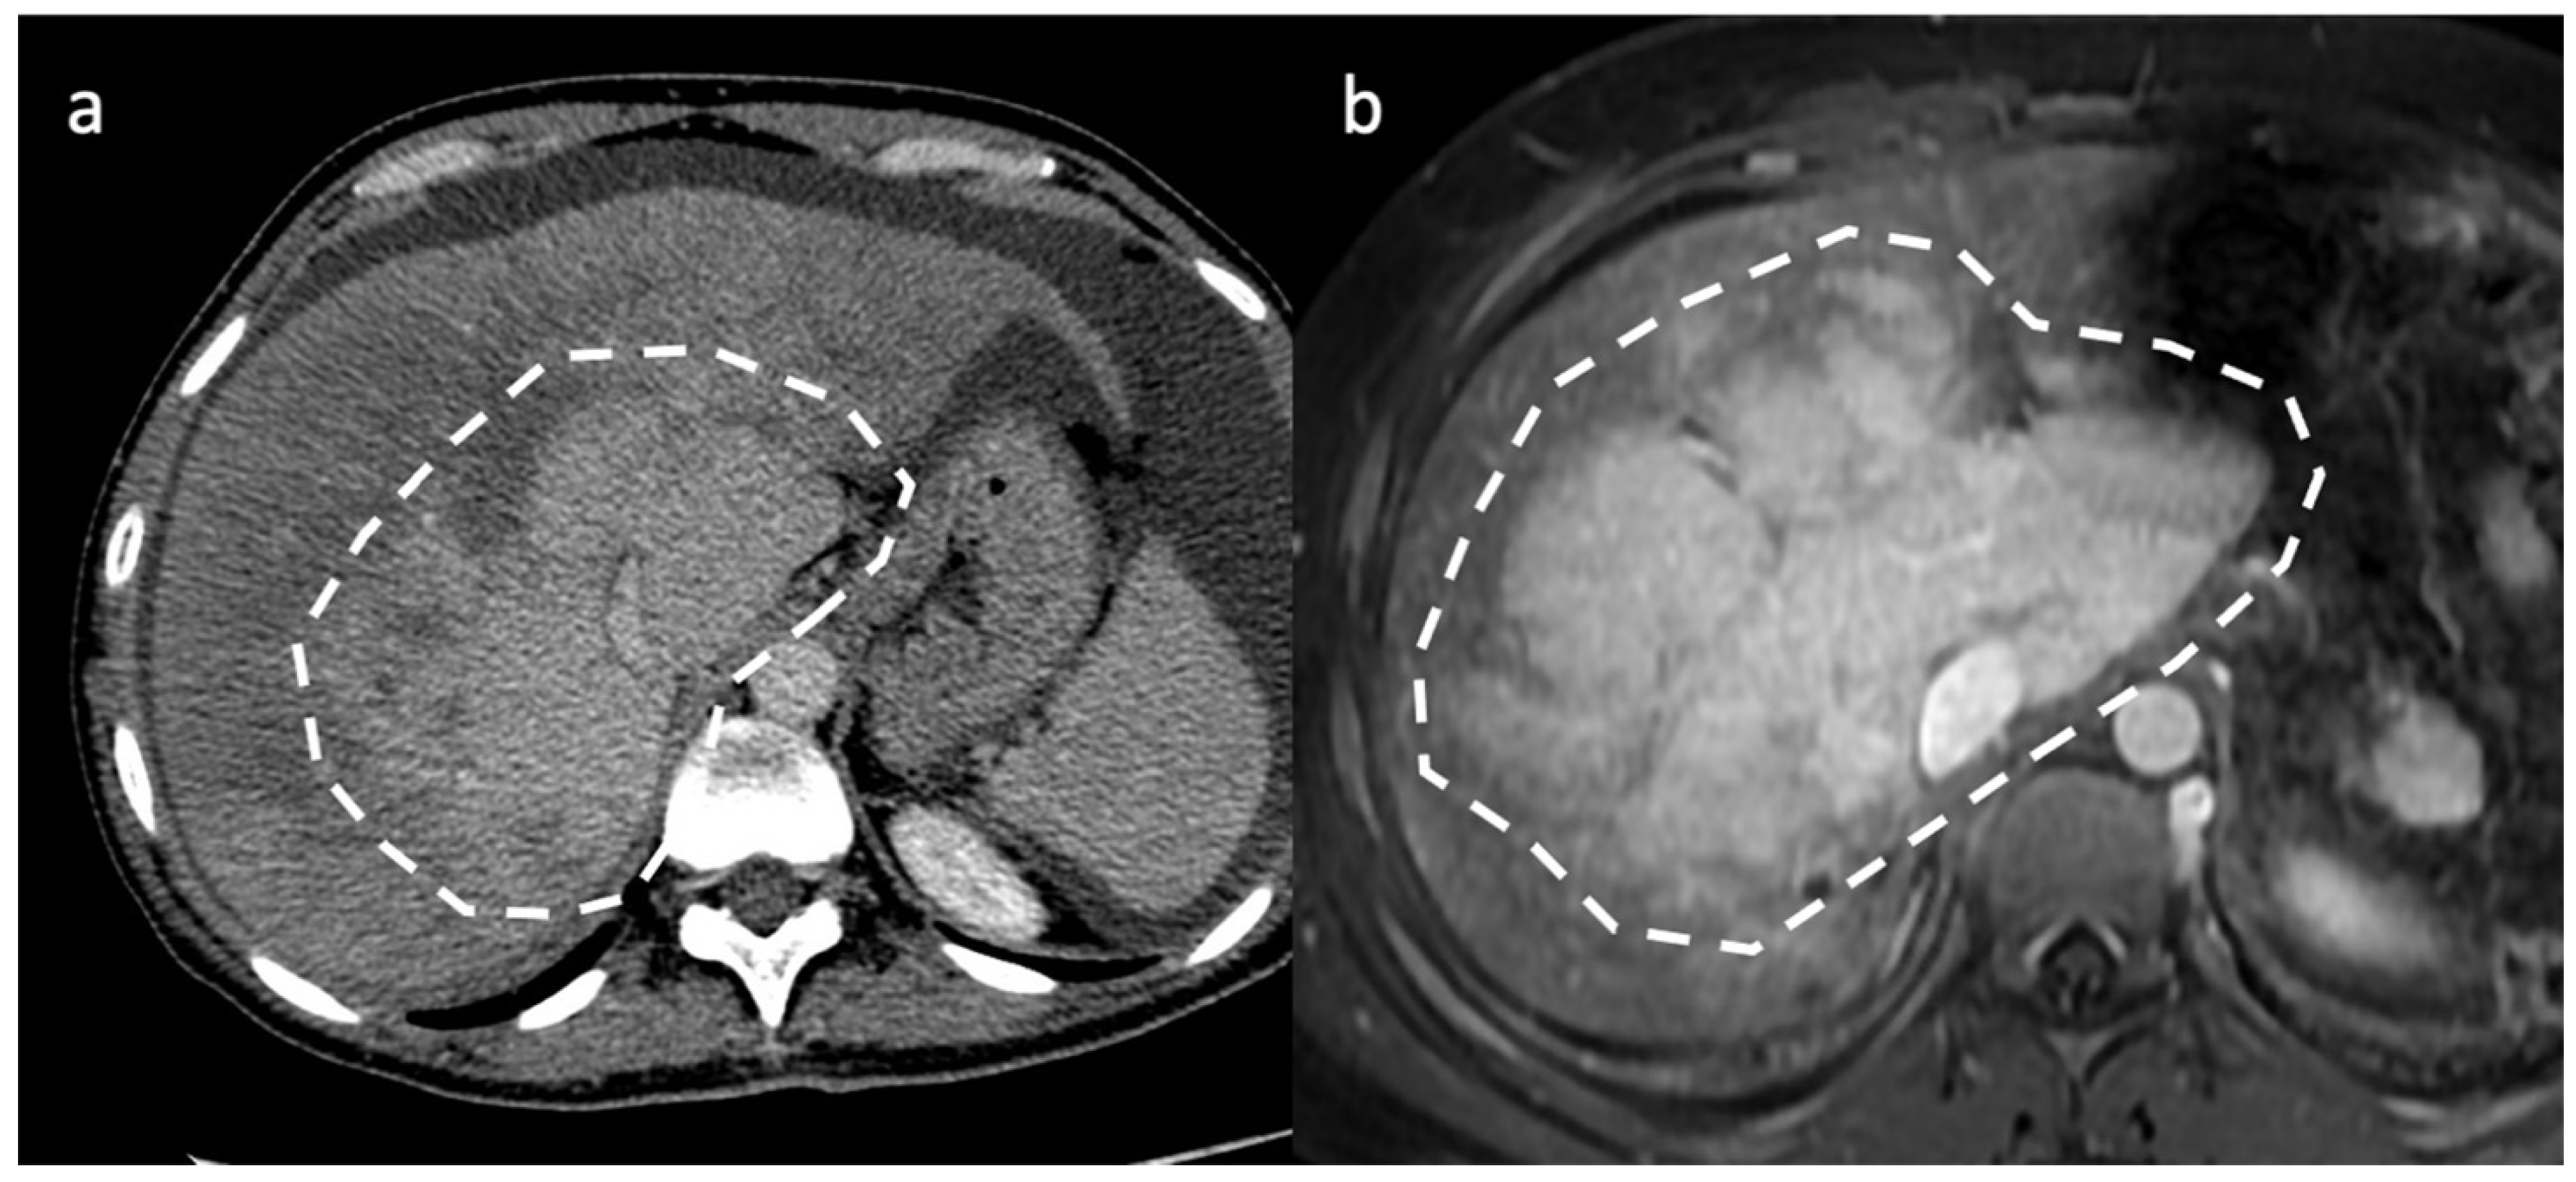

- Indirect signs: non-specific. They represent the consequences of long-standing hepatic venous impairment, including liver parenchymal changes with fibrosis and atrophy of involved segments and hypertrophy of unaffected territories (e.g., caudate lobe hypertrophy). On CT and MRI, centrilobular or sinusoidal congestion, represented as heterogeneous ”mosaic” enhancement after contrast media is also characteristic. Other signs include ascites, portal hypertension, and the presence of benign regenerative nodules, as well as hepatocellular carcinoma [6].

3.2. Computed Tomography and Magnetic Resonance: What to Look For

| CT | Liver morphology alteration Acute phase: “zonal” or “flip-flop” perfusion Chronic phase: “mosaic” perfusion Extra- and intra-hepatic collaterals Site and extension of thrombosis Pre-endovascular treatment assessment Hepatic artery and caudate vein enlargement Hepatic Nodules Ascites and caudal lobe enlargement |

| MRI | Characterization of nodules (FNH-like nodules vs. HCC) T1-w decreased signal in hypoperfused regions, corresponding to high T2-w SI T2*-w flow void corresponding to thrombus. Hypointensity along the occluded vessels |